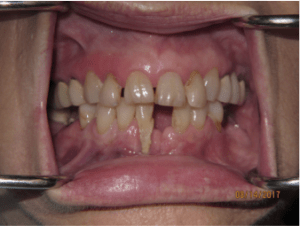

Before:

Before:

Before:

Before:

Before: